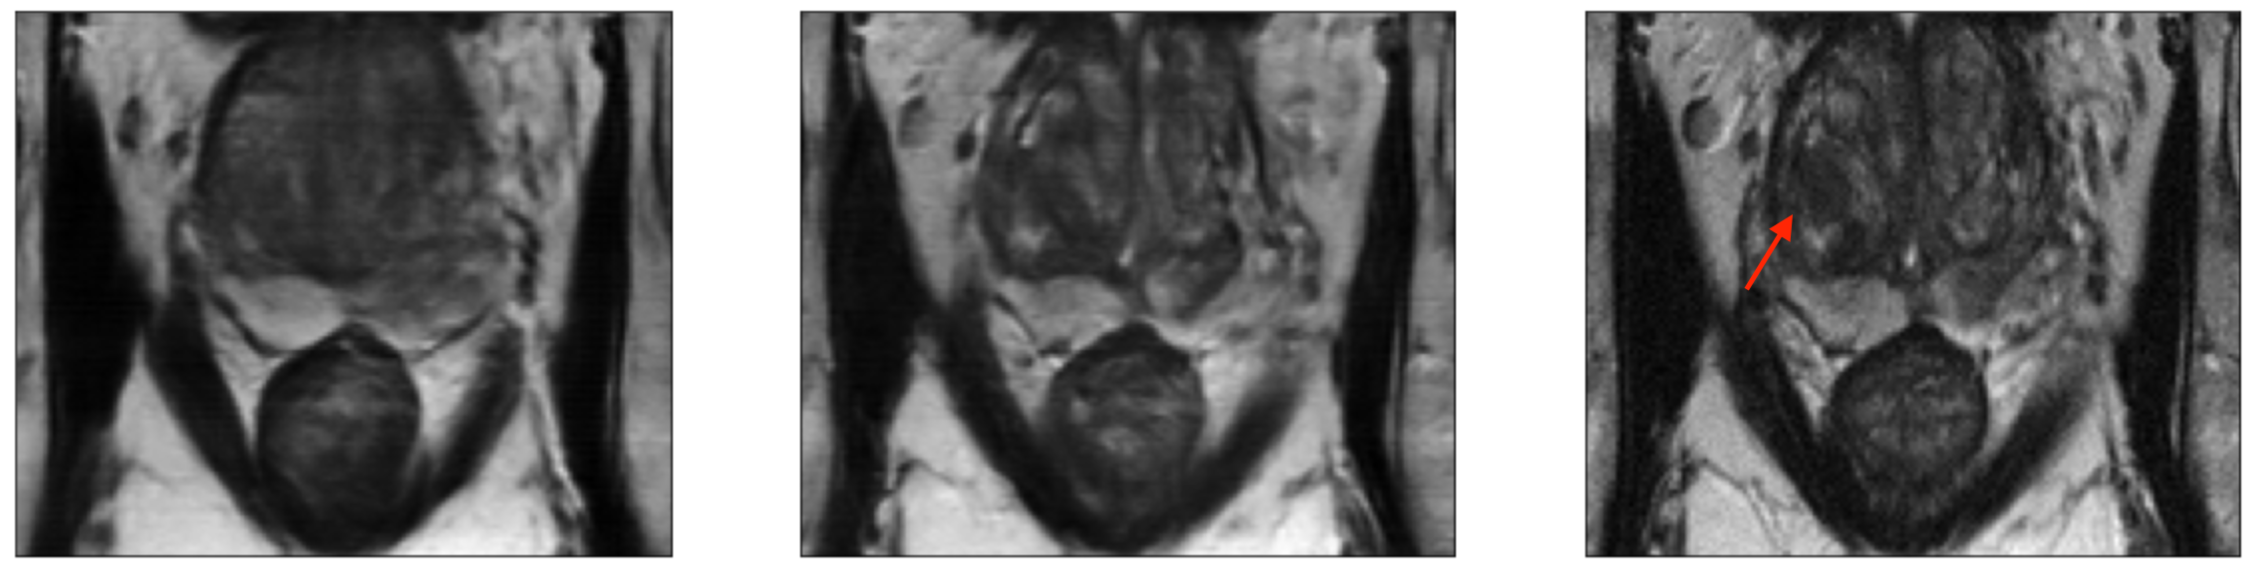

To understand the reason behind poor accessibility of mr, we first shed light on the workings of the pipeline. Figure 2 (c) depicts the full mr pipeline. mr imaging is an indirect imaging process in which the mr scanner subjects the human body with magnetic field and radio-frequency signals and measures the subsequent electromagnetic response activity from within the body. These measurements are collected in the Fourier space, also known as -space (see section in [7]) (stage S1 in figure 2 (c)). The D volumetric image of the anatomy is reconstructed from these k-space measurements using a multi-dimensional inverse Fourier transform (stage S2). The images are then finally interpreted by sub-specialized radiologists who render the final diagnosis (stage S3). The reason behind mr’s diagnostic success is its ability to generate these high-fidelity images with excellent soft-tissue contrast properties, because such images enable the human radiologists to easily discern the pathology accurately. The quality of the images is directly related to the quantity and the quality of the k-space measurements acquired: large quantities of high-quality measurements results in a high-quality image. This in-turn necessitates the need for 1) expensive specialized scanners installed in special purpose imaging centers to collect large quantities of high-quality k-space data, 2) execution of long and complex data acquisition protocols to reconstruct the high-fidelity images exhibiting multiple contrasts, and 3) sub-specialized radiologists to interpret the reconstructed images. All these factors prevent mr scanning to be used as a tool closer to poc for early and accurate disease identification. Instead its use is predominantly limited to validating a clinical hypothesis at the end of the diagnostic chain. With the motivation of improving accessibility of mr, researchers have proposed multiple solutions to simplify the pipeline. These include designing novel acquisition protocols to acquire the k-space data [32, 14], learning the under-sampling pattern over k-space data matrices so that the image quality is not compromised [2, 73, 64, 25], faster data acquisition and image reconstruction from the under-sampled k-space data, and for simultaneous classification and image-reconstruction using under-sampled k-space data [31, 39, 40, 70, 44, 20]. While these efforts have expedited the data acquisition process, the requirement to generate high-fidelity images still necessitates the use of expensive scanners and the need for a sub-specialized radiologist to interpret them. Furthermore, image generation also imposes limits on how much one can under-sample the -space. For instance, [44] reports that reconstructed images started missing clinically relevant pathologies if we sample less than of the data. This phenomenon can be observed in Figure 1, which shows images reconstructed by a state-of-the-art reconstruction model [56] using different levels of sampling. A clearly visible lesion in the high resolution image is barely visible in the image generated using data.

Figure 5 and table 3 give the auc, Sensitivity, and Specificity of the emrt model at different sampling rates and compares its performance to the model. We observe that at high sampling rates, the performance of emrt, in terms of auc and sensitivity-specificity, does not deteriorate significantly in comparison to the dl trained trained on high-fidelity images reconstructed using the full k-space data. This experiment demonstrates that if the goal is to simply infer the presence/absence of the disease, without the concern to reconstruct a high-fidelity image, then we can afford to significantly under-sample the k-space data (as low as %) without any significant loss in performance. This is in contrast to [44], which reports that in the Fastmri challenge, all submissions had reconstructed images that started missing clinically relevant pathologies at sampling rates less than of the data. Figure 1 shows the sequence of images reconstructed from the k-space data corresponding to the sampling patterns learnt by emrt. One can clearly see that the pathology visible is the image reconstructed from the full k-space is hard to discern in images generated from under-sampled data. Furthermore, it becomes successively hard to identify the pathology as we decrease the amount of data used.